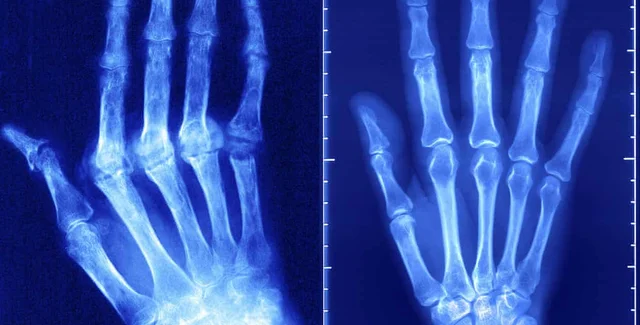

Число случаев аутоиммунных заболеваний увеличивается на 3-9% в год | Фото: The Guardian

Аутоиммунные заболевания варьируются от диабета 1 типа до ревматоидного артрита, воспалительных заболеваний кишечника и рассеянного склероза.